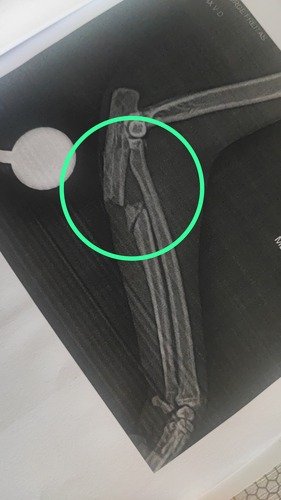

Aqui algumas de suas fraturas:

Vitória (nome que demos a ela por sua força de sobreviver a uma queda de 18 metros!) chegou com múltiplas fraturas, feridas graves e muita dor. Passou por exames, ficou internada, foi operada e agora luta para se recuperar. Ela precisou de cirurgia com barra de titânio, tratamento de feridas expostas e acompanhamento intensivo.